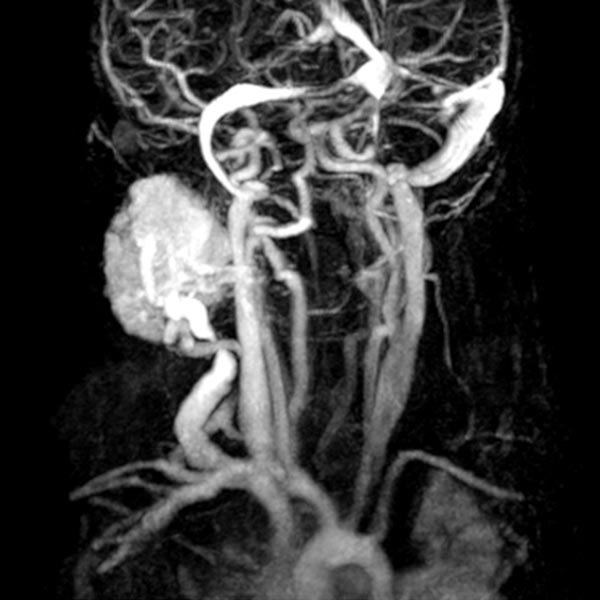

The girl is now 24 months old and the mass has not regressed. It is visible from the outside and causes the patient clear pressure pain. Dynamic contrast-enhanced MR angiography shows the intense enhancement of the infantile hemangioma. The main venous drainage is via the external jugular vein, which shows a relevant stenosis of the outflow in the proximal area.

In view of the lack of regression, probably also caused by the relevant stenosis of the venous outflow, the decision to embolize the hemangioma was made in the 24th month of life in order to induce regression of the mass. In a first step during intervention, the venous outflow (right external jugular vein) was cannulated retrogradely from transvenously.

Digital subtraction angiography (DSA) after injection into the right common carotid artery shows the infantile hemangioma mainly supplied from the external carotid artery, as expected.